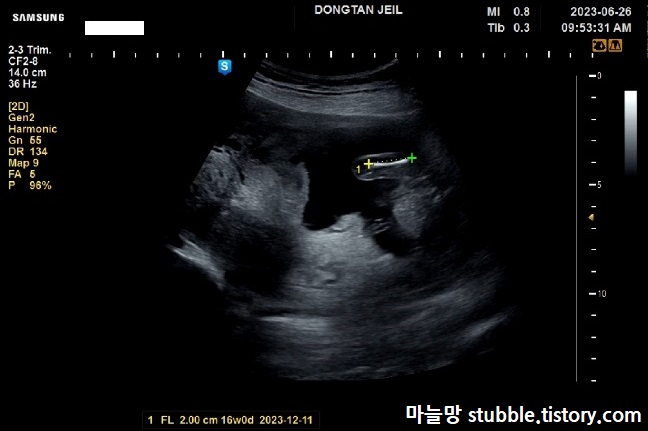

다리 부분이라서 이때 성별을 확인하려고 하였으나, 넓적다리의 뼈 길이(FL)만 쟀어요. 주수보다 살짝 작아요.